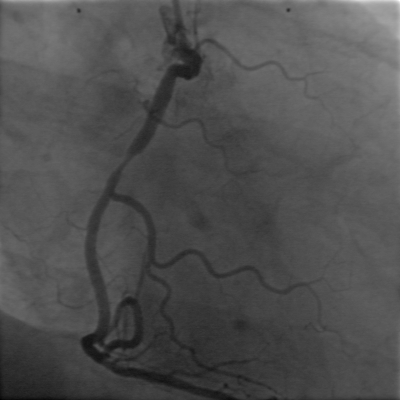

5.1原图